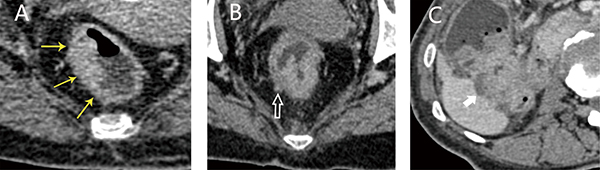

According to the classification method previously reported by Kazuhito Sato et al. [27], the wall deformity was scored from 1–4 as follows: 1 – lesions smaller than 1 cm and 2–4 – lesions with lengths equal to or greater than 1 cm. Specifically, a score of 2 represented an angle less than 90° formed by the outline of the lesion and the outer edge of the intestinal tract, whereas a score of 3 indicated an angle that was equal to or greater than 90°. The apple core sign was classified as a score of 4 (Figure 3). The ray sum images were used to show the best angle for measurement. In conventional CT images, we identified the largest dimension of the tumor by reconstruction of the original images and then measured the desired angle.

Figure 3: Four types of wall deformations revealed using MDCT following a water enema (A, B) and ray sum images (C, D). A: a score of 1 indicates a lesion smaller than 1 cm; B: a score of 2 indicates a lesion angle less than 90°; C: a score of 3 indicates a lesion angle greater than 90°; D: a score of 4 indicates the apple core sign intestinal wall deformation.

The traditional colorectal cancer imaging staging method evaluates the deformation of the bowel wall at the lesion based on the AJCC tumor TNM system. Because of the low resolution of CT [32], T1 and T2 tumors were collectively referred to as ≤ T2 stage. According to previous studies [6, 18], CT images containing ≤ T2 tumors showed lesions with smooth outer edges of the intestinal wall, whereas T3 tumors exhibited rough serous layers with the presence of speculation. T4 tumors had infiltrated the peritumoral fat plane, as evidenced by streaks and nodules, or had infiltrated adjacent organs (Figure 4). According to this conventional method, three experienced radiologists staged the tumors of patients in the validation cohort independently. If their diagnosis was inconsistent, we adopted the result of their agreement or the conclusion of the radiologist with more experience.

Figure 4: Axial images of tumors of various stages obtained using a traditional method. (A) T2 stage, lesions exhibited a smooth outer edge; (B) T3 stage, the edge of the intestinal wall shows sharp corners; (C) T4 stage, the lesion had invaded the inferior margin of the adjacent liver.